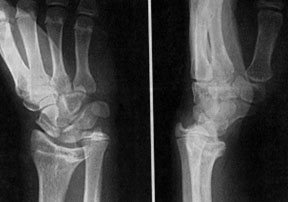

Рентгенограмма кисти с деформацией Маделунга

Диагноз устанавливают на основании характерных клинических и рентгенологических проявлений. При рентгенологическом исследовании выявляют относительное укорочение лучевой кости на 45 см и скошенность суставной поверхности дистального эпифиза лучевой кости в ладонную и локтевую сторону, что создает впечатление подвывиха кисти (костей запястья). Полулунная кость как бы нависает над ладонным краем эпифиза лучевой кости. Высота дистального эпифиза по лучевой стороне значительно превосходит его высоту по локтевой стороне, а раннее закрытие эпифизарной ростковой зоны по локтевой и ладонной стороне создает ладонный и локтевой наклон суставной поверхности. Отмечают изменение расположения проксимального ряда костей запястья, они образуют клин, на вершине которого располагается полулунная кость. Головка локтевой кости находится в положении вывиха (в дистальном направлении) и смещена в тыльном направлении относительно лучезапястного сустава. Обычно расположена на уровне основания пястных костей.